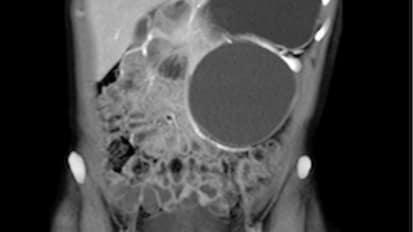

Johns Hopkins Research Shows Potential for Cure for Polycystic Kidney Disease

Working both with mice and with 3D models of kidney cysts, genetics researcher Liudmila Cebotaru found that introducing a specific CFTR corrector slowed cystic growth.